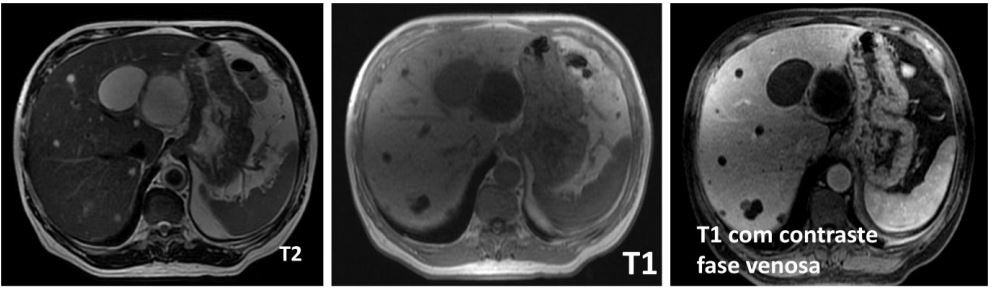

Homem, 46a, acompanhado há um ano devido 2 cistos simples hepáticos em segmentos II e III, de 2,3cm e 3,1cm, respectivamente. Seis meses após, iniciou quadro de desconforto abdominal, adinamia, com piora progressiva, nos últimos 10 dias e perda ponderal de 1,5kg neste período. Apresenta os seguintes exames laboratoriais: Hb= 12,7g/dl; Leucócitos= 16.500mm3 , com 2% de bastões; Plaquetas= 524.000mm3 ; Bilirrubinas total= 0,9 mg/dL; Albumina= 3,9mg/dL; Fosfatase alcalina= 149U/L ; Gamaglutamiltransferase= 223U/L; AST= 56U/L; ALT= 89 U/L.

Realizou ressonância magnética nuclear (RMN) de abdome com as imagens abaixo:

Mediante a história clinica e estes achados de RMN, o diagnóstico e a conduta são, respectivamente: